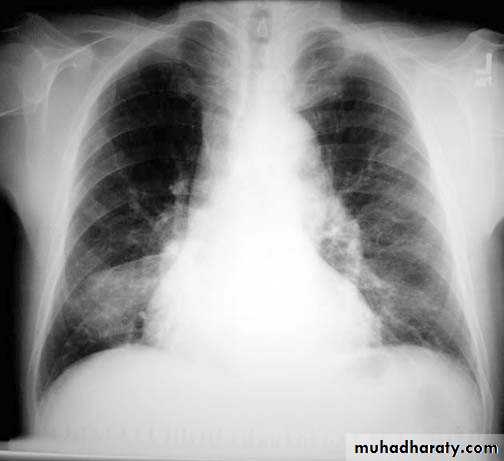

• Pleural effusion : collection of fluid within the pleural space. This can be further divided into Transudate , exudate, according to protein content .Other type of fluid collection within pleural space are

• Chest x-rays are the most commonly used examination to assess for presence of a pleural effusion, however it should be noted that on a routine erect frontal chest x-ray as much as 200-500 ml of fluid is

• required before it becomes evident .

blunting of the costophrenic angle

blunting of the cardiophrenic angle

fluid within the horizontal or oblique fissures

eventually a meniscus will be seen, on frontal films seen laterally and gently sloping medially

with large volume effusions, mediastinal shift occurs away from the effusion

Pleura effusion signs

Obliteration of costo-pherinic anglesMeniscus sign

Lenticular sign